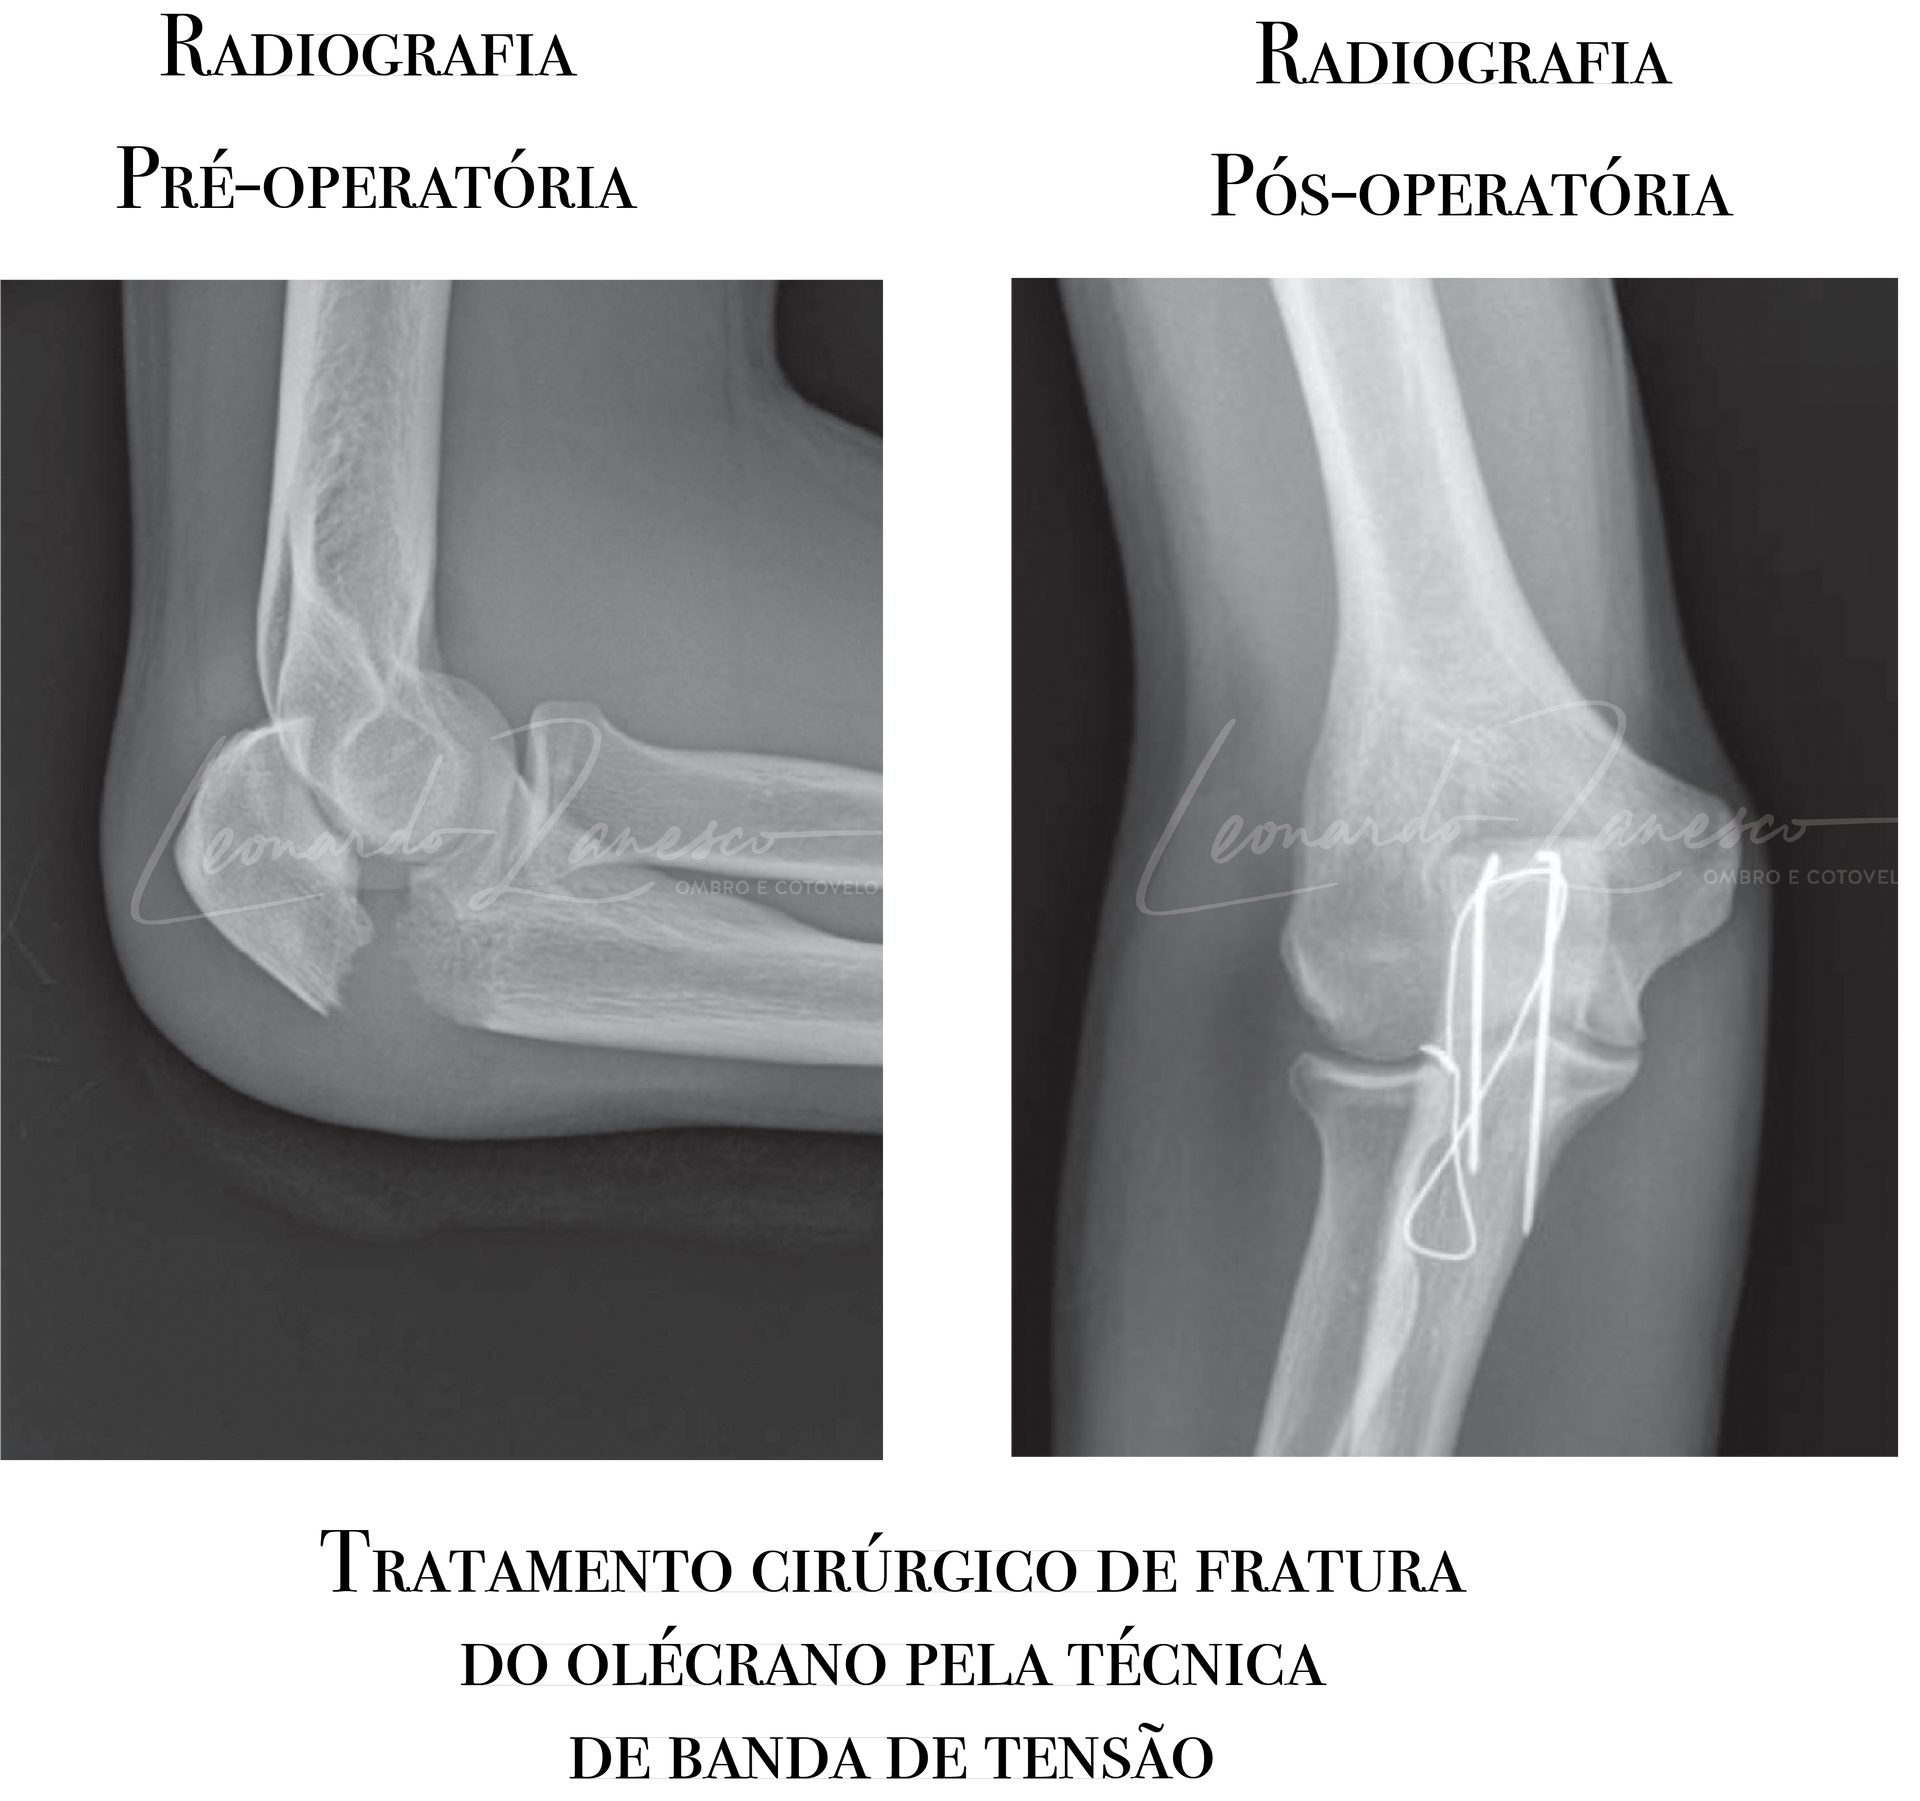

Banda de tensão com fios de Kirschner e cerclagem:

Técnica

menos invasiva, de custo menor, preferida em

traços simples e transversos (sem cominuição). Seu principal ponto de atenção é a

proeminência do material, frequentemente levando à retirada de implante.